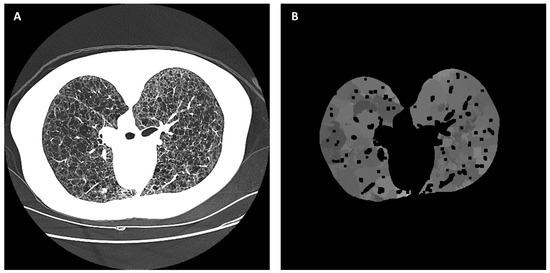

2.4. Automated Cyst Segmentation